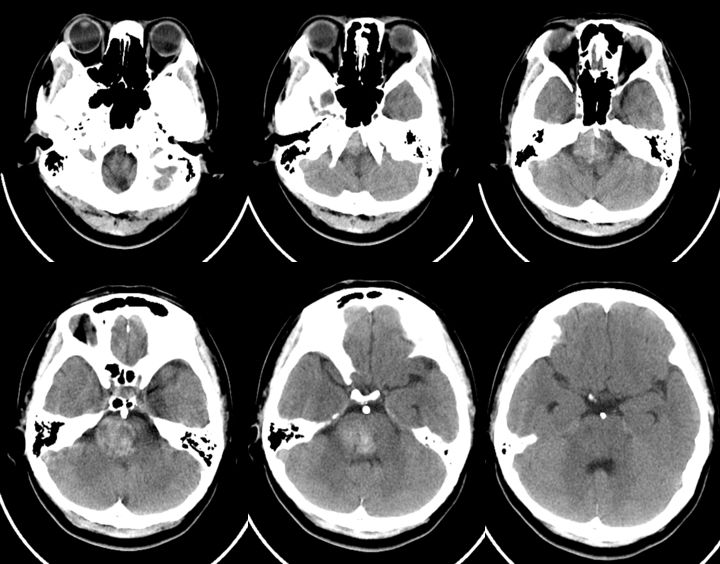

当地医院头CT:右侧脑干占位(2019-09-06)(图1)。

图1

2、头部核磁共振显示:脑干占位性病变,边界较清晰,较大层面大小约35 mmx25 mm。MRA显示:基底动脉夹层动脉瘤。DSA显示,基底动脉巨大夹层动脉瘤,最大长径为:10.8 mm,最大短径为3.2 mm。根据患者症状及影像学诊断,基底动脉巨大夹层动脉瘤进行性增大压迫脑干,不排除脑干水肿可能,亟待手术治疗。

5、术后患者恢复良好,复查CT与术前无明显改变。查体:神志清,精神可,双侧瞳孔等大等圆,复视、吞咽困难、饮水呛咳较入院时明显改善,右侧肢体肌力5级,左侧肢体肌力4级,四肢肌张力正常,双侧病理征阴性(图12)。

图12